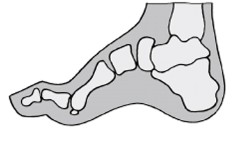

Sperone calcaneare talalgia

- Sovraccarico dell’arco longitudinale - irritazione periostale

- Dolore localizzato all’inizio della aponeurosi plantare